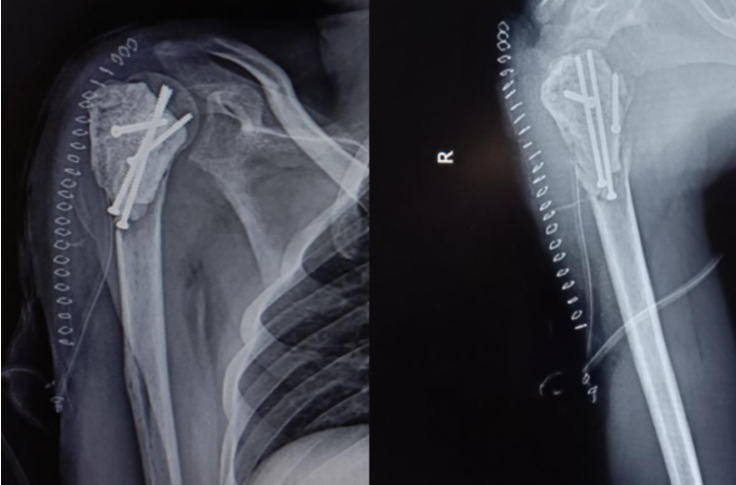

Soft-tissue dissection included carefully incising the sinus tract created during the biopsy through its entire length. The surgical field was circumferentially lined with hydrogen-peroxide soaked mops as a form of chemical cauterization, and two separate trolleys were maintained – one for instruments contaminated with tumor material and the other for sterile instruments. After adequate exposure, tumor material was scooped out with a curette, with the tumor cells carefully removed using a high- speed burr to achieve negative margins. Utmost care was taken to not breach the anterior or medial wall of the proximal humerus while using the burr under fluoroscopic guidance. A final hydrogen-peroxide wash was given. Reconstruction of the void started with a basal layer of tri-cortical iliac crest bone graft. Under fluoroscopic guidance, 4 fully-threaded cancellous screws were then inserted in a pre-determined sequence of different orthogonal plains to create a scaffold (2 in rostro-caudal manner, 1 antero-posterior, and 1 transverse) (Fig.3) .

Figure 3: Cancellous screw scaffold created in the tumor void.

Low-viscosity bone cement was prepared and poured over the scaffold (Fig.4).

Figure 4: Tumor void filled with allograft, screw scaffold, and bone cement.

The treatment modalities for management of GCT’s include chemotherapy, radiotherapy, embolization, cryosurgery, and surgery. Among all treatment methods, surgery remains the only effective treatment for GCT, in most cases. The operative method is determined by the surgical stage of the giant-cell tumor, its size and location, age of the patient, and whether it is a primary tumor or a recurrence [6]. Nonetheless, the ideal form of surgery for this tumor, particularly when arising near joints or when present in weight-bearing bones, remains controversial [7], especially in Campanacci Grade III giant cell tumors, as their massive sizes provide an uphill task in reconstruction and demands case-specific planning from the surgeons. Surgical options include intralesional curettage with bone grafting and/or cement or segmental resection and reconstruction with allograft or prosthesis. The goal of surgery in current times is not only to prevent recurrence by completely removing the tumor but also to maintain adjacent joint function. The evaluation of function, described by Musculoskeletal Tumor Society score (MSTS) adequately gauges the patient’s acceptability of a given procedure [8]. While wide resection and reconstruction minimize tumor recurrence, it fails to provide acceptable functional outcomes, especially in the shoulder joint after treatment of proximal humerus lesions. Intralesional curettage has a higher reported recurrence rate but performs much better on the acceptability scale. Therefore, joint-sparing surgery and careful curettage with the use of adjuvants should be the treatment of choice whenever possible [9]. Grade III osteoclastoma can be treated by intralesional excision, provided the articular surfaces and part of the metaphysis are intact [8]. In younger patients, intra-lesional curettage and reconstruction provide optimum outcomes with minimal chances of recurrence and higher MSTS scores [10]. This has been a major shift in management as high-grade GCT’s were conventionally treated with wide resection due to fear of recurrence [11]. This shift can be attributed to adoption of combined cauterization methods – mechanical (high speed burr), chemical (use of adjuvants like phenol, Hydrogen peroxide, ethanol, and zinc chloride) [12], and thermal (use of bone cement in reconstruction of the cavity) [13], to attenuate the risk of recurrence. Reconstruction using the sandwich technique – in which allograft is placed in the subchondral region and is overlaid with a layer of gelfoam and the rest of the cavity is filled with cement [14] Sandwich technique has been highly popular since first described by Campanacci as it circumvents the disadvantages of both, the bone cement and bone graft when used alone [14,15]. While bone cement helps with immediate stability and early post-operative mobilization, tumoricidal effect via heat generation and easier detection of recurrence as it is easily visualized at the bone-cement interface [16]. It also provides a technical advantage as the plasticity of cement during polymerization allows complete filling of a tumor cavity with irregular confines, and the polymer can be firmly molded around metallic implants [17]. However, it may result in but subchondral articular cartilage damage and joint destruction, and hence, increases the risk of requiring arthroplasty in the long term [13]. The shortcomings are tackled by the layer of subchondral bone graft, as it limits the thermal destruction of the cartilage, as well as provides structural support to the joint. Another advantage that using bone graft provides is a permanent reconstruction of the joint once the graft has completely incorporated into the native bone. The two components of the sandwich technique have a synergistic effect of reducing post-operative complications without increasing the rates of recurrence [18]. However, the vulnerability of this technique of curettage and cementation lies in the high fracture risk, which is caused due to the early loading of the bone and sub-optimal fixation of the cement in the cavity [19]. To alleviate the risk of post-operative fractures, various methods of internal fixation have been tried. These include, in increasing order of stability, Steinmann pins, interdigitating screws [17,20], and locking plates [21]. While inter-digitating screws were relatively less stability as compared to locking plates, they compensated in terms of technical feasibility as they could be inserted directly under vision [17], reduction in operative time, and minimal dissection was required further than what was already done for the curettage, all of which the author believed to be pivotal in the outcome for this patient with a deficient immune system [20]. Toy et al., in a biomechanical study of distal femur defects, furthered the case for this system. They proved that since the screws crossed the midline and had purchase on healthy bone on the opposite side, they allowed the cement mantle to remain stable, thus transferring most of the load to the bone away from the defect and therefore, if a fracture were to occur after this reconstruction, it would most likely be an fracture away from the cavity, which would not only be easier to treat but also would not necessitate any removal of implant. Even though the findings of this study cannot be directly applied to other anatomical sites, the author believes that the principles of augmenting the cementation with screws in a cross-beam construct can be adopted and applied to create a configuration custom to the area of the lesion, as it is the configuration of the screws and not the screws themselves which helps provide the stability. This could help surgeons circumvent the longer incisions and use of excessive hardware while achieving a similar level of stability and ease of future implant removal. The author used an interdigitating cancellous screw in the cavity of the proximal humerus in a pre-determined sequence to cater to the needs of the shoulder joint during its movements, protecting the soft tissue envelope. The screws helped create a scaffold and increase the core strength of the construct. Complimenting this with bone cement and a layer of sub-chondral bone graft to fill the cavity helped us achieve a stable construct in a minimally invasive way.(Fig.5)

Figure 5: Fixation using 4 fully threaded cancellous screws and bone cement.